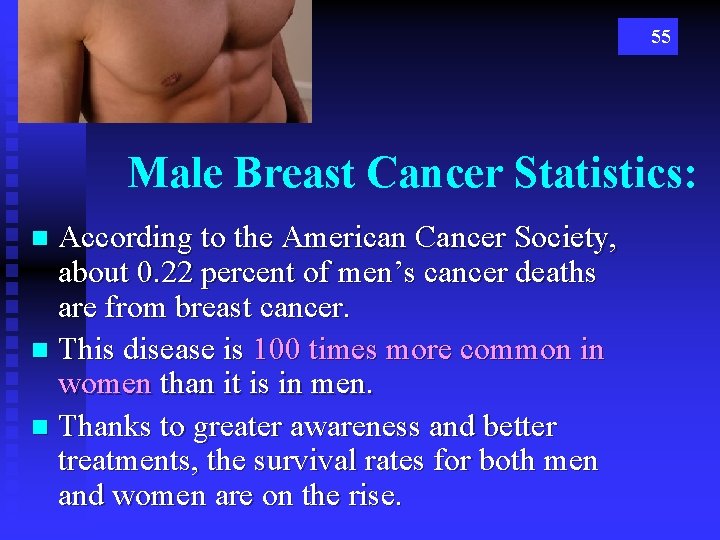

55 Male Breast Cancer Statistics: According to the American Cancer Society, about 0. 22 percent of men’s cancer deaths are from breast cancer. n This disease is 100 times more common in women than it is in men. n Thanks to greater awareness and better treatments, the survival rates for both men and women are on the rise. n